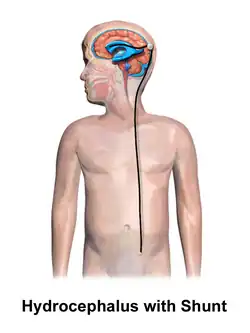

Hydrocephalus is typically treated through surgery. One option is the placement of a shunt system.[1] A procedure called an endoscopic third ventriculostomy has gained popularity in recent decades, and is an option in certain populations.[4] Outcomes are variable, but many people with shunts live normal lives.[1] However, there are many potential complications, including infection or breakage.[4] There is a high risk of shunt failure in children especially.[4] However, without treatment, permanent disability or death may occur.[1]

Ventriculoperitoneal shunt placement in child with hydrocephalus

Hydrocephalus is treated through surgery by creating a way for the excess fluid to drain away. An external ventricular drain (EVD), also known as an extraventricular drain or ventriculostomy, provides relief in the short term.[48] In the long term, some people will need any of the various types of cerebral shunts.[48] It involves the placement of a ventricular catheter (a tube made of silastic) into the cerebral ventricles. This creates a way to bypass the flow obstruction/malfunctioning arachnoidal granulations. The excess fluid drains into other body cavities where it can be resorbed. Most shunts drain the fluid into the peritoneal cavity (ventriculoperitoneal shunt).[49] Other shunts drain the fluid into the right atrium (ventriculoatrial shunt), pleural cavity (ventriculopleural shunt), and gallbladder.[49]